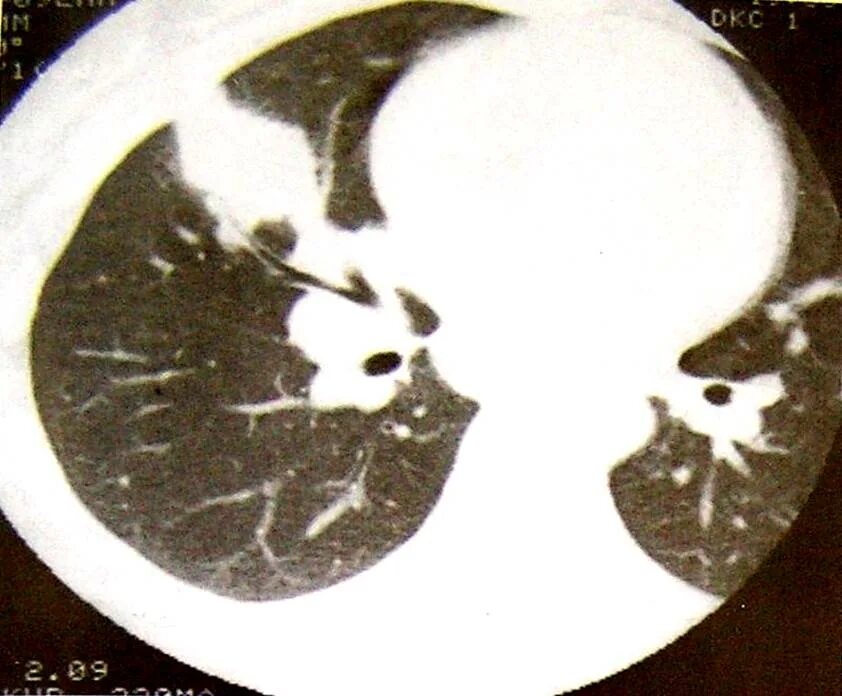

Утолщение бронха